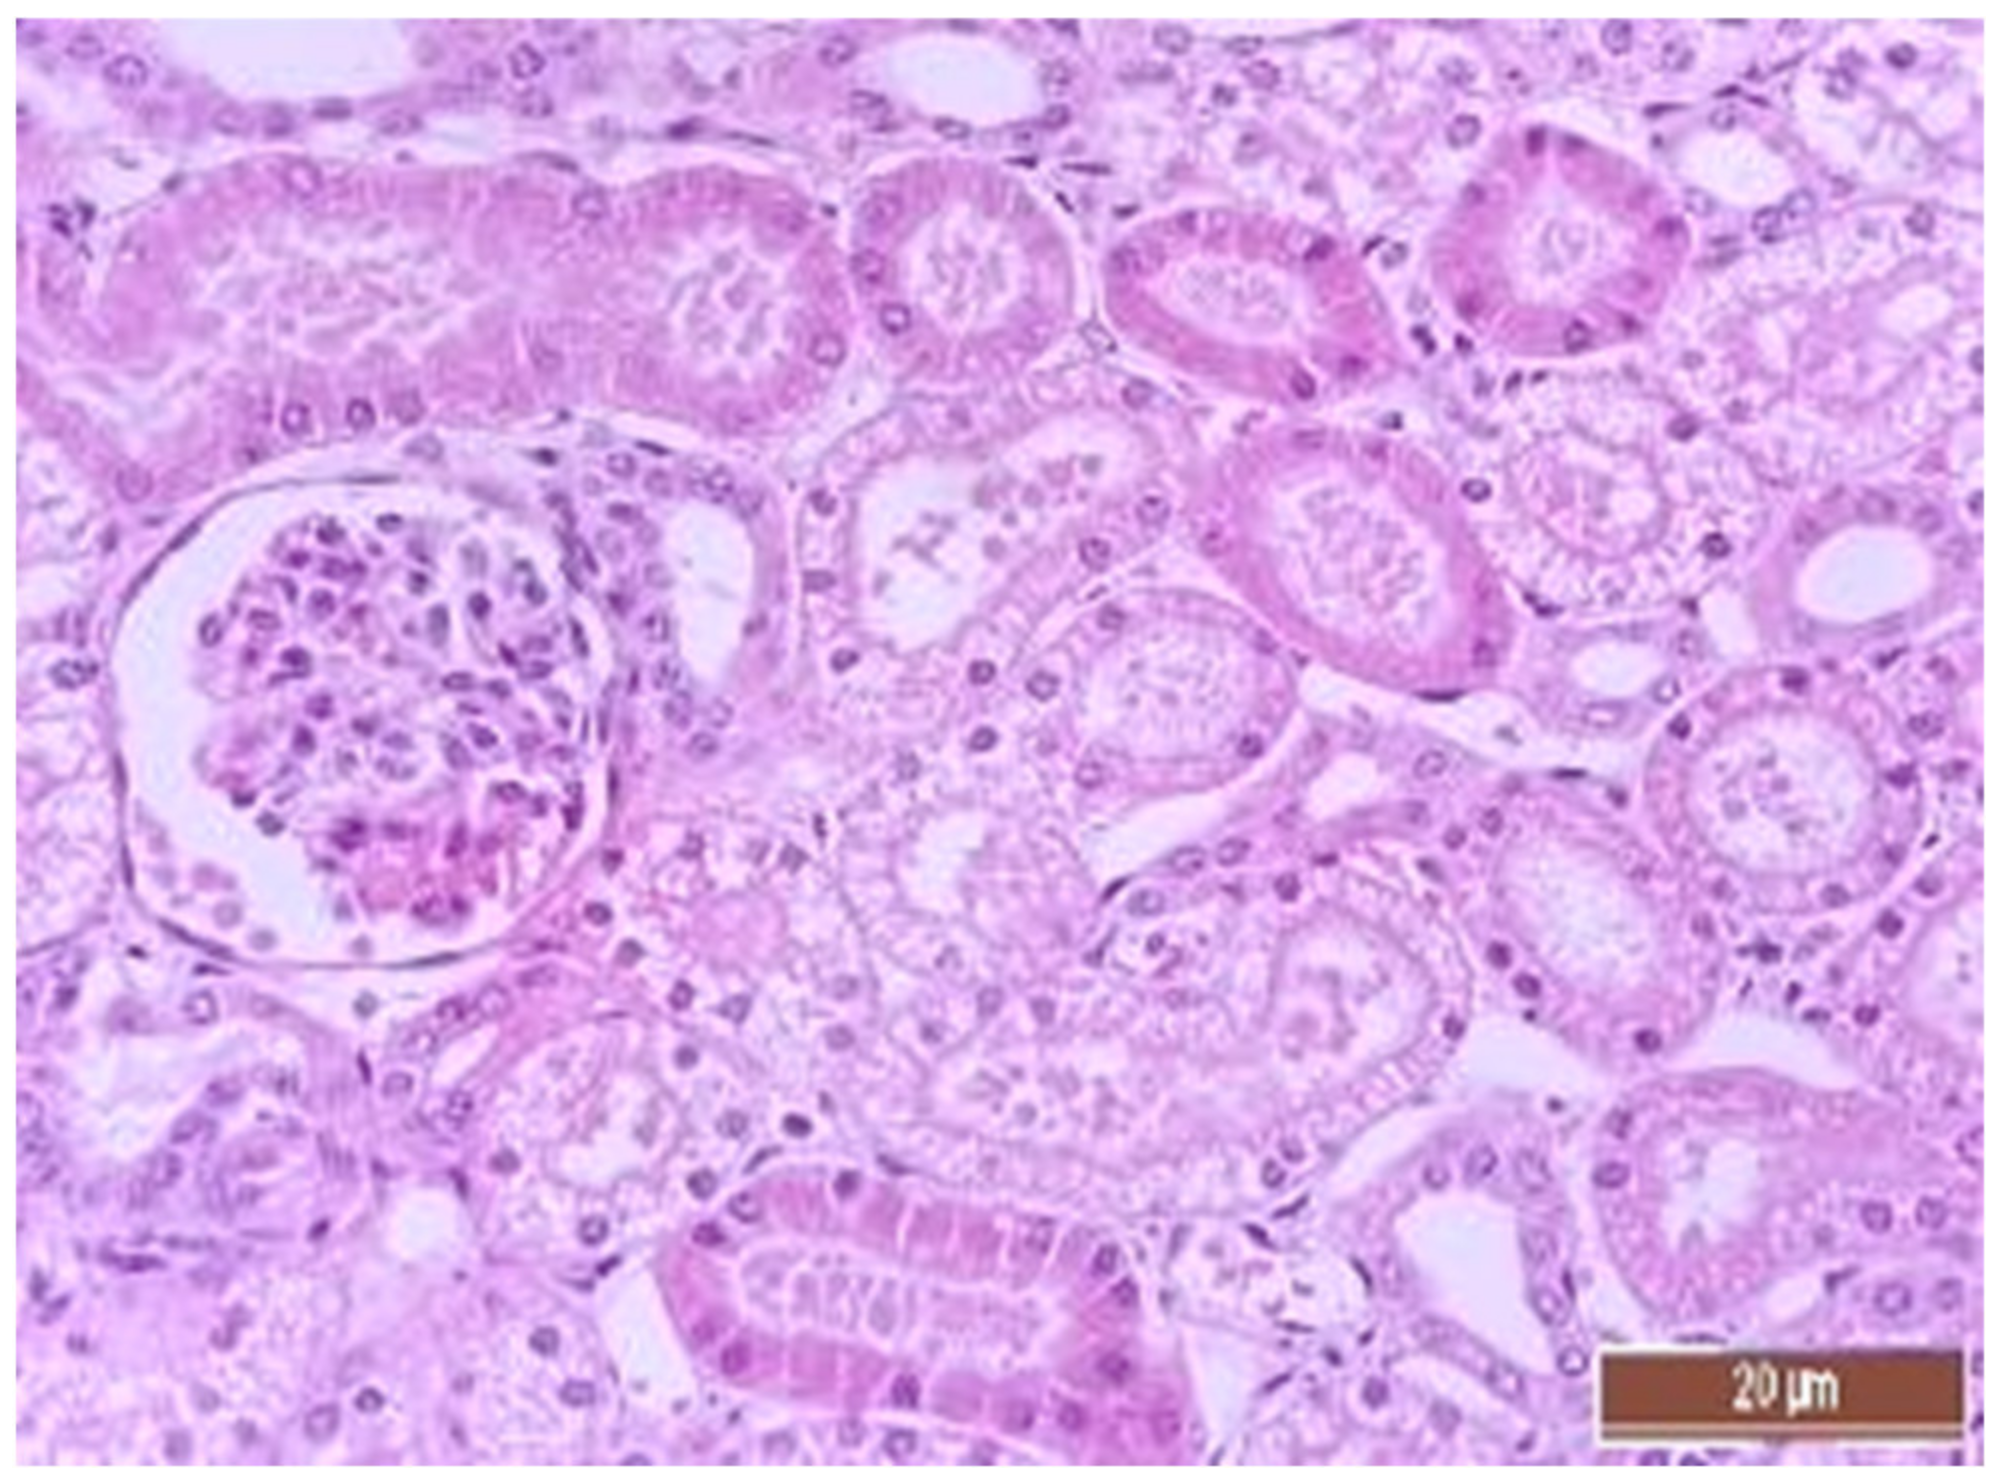

3.4. Pathology of Kidneys

| Value | Group | Value, Point | Mann–Whitney U-Test |

|---|---|---|---|

| Dystrophy of the epithelium of the tubules | CPB-contr, n = 25 | 2 (1; 3) | p = 0.49 |

| CPB-NO, n = 25 | 1 (1; 2) | ||

| Lymphoplasmocytic infiltration | CPB-contr, n = 25 | 0 (0; 1) | p = 0.37 |

| CPB-NO, n = 25 | 1 (1; 1) | ||

| Hyperemia | CPB-contr, n = 25 | 2 (2; 3) | p = 0.55 |

| CPB-NO, n = 25 | 3 (2; 3) |